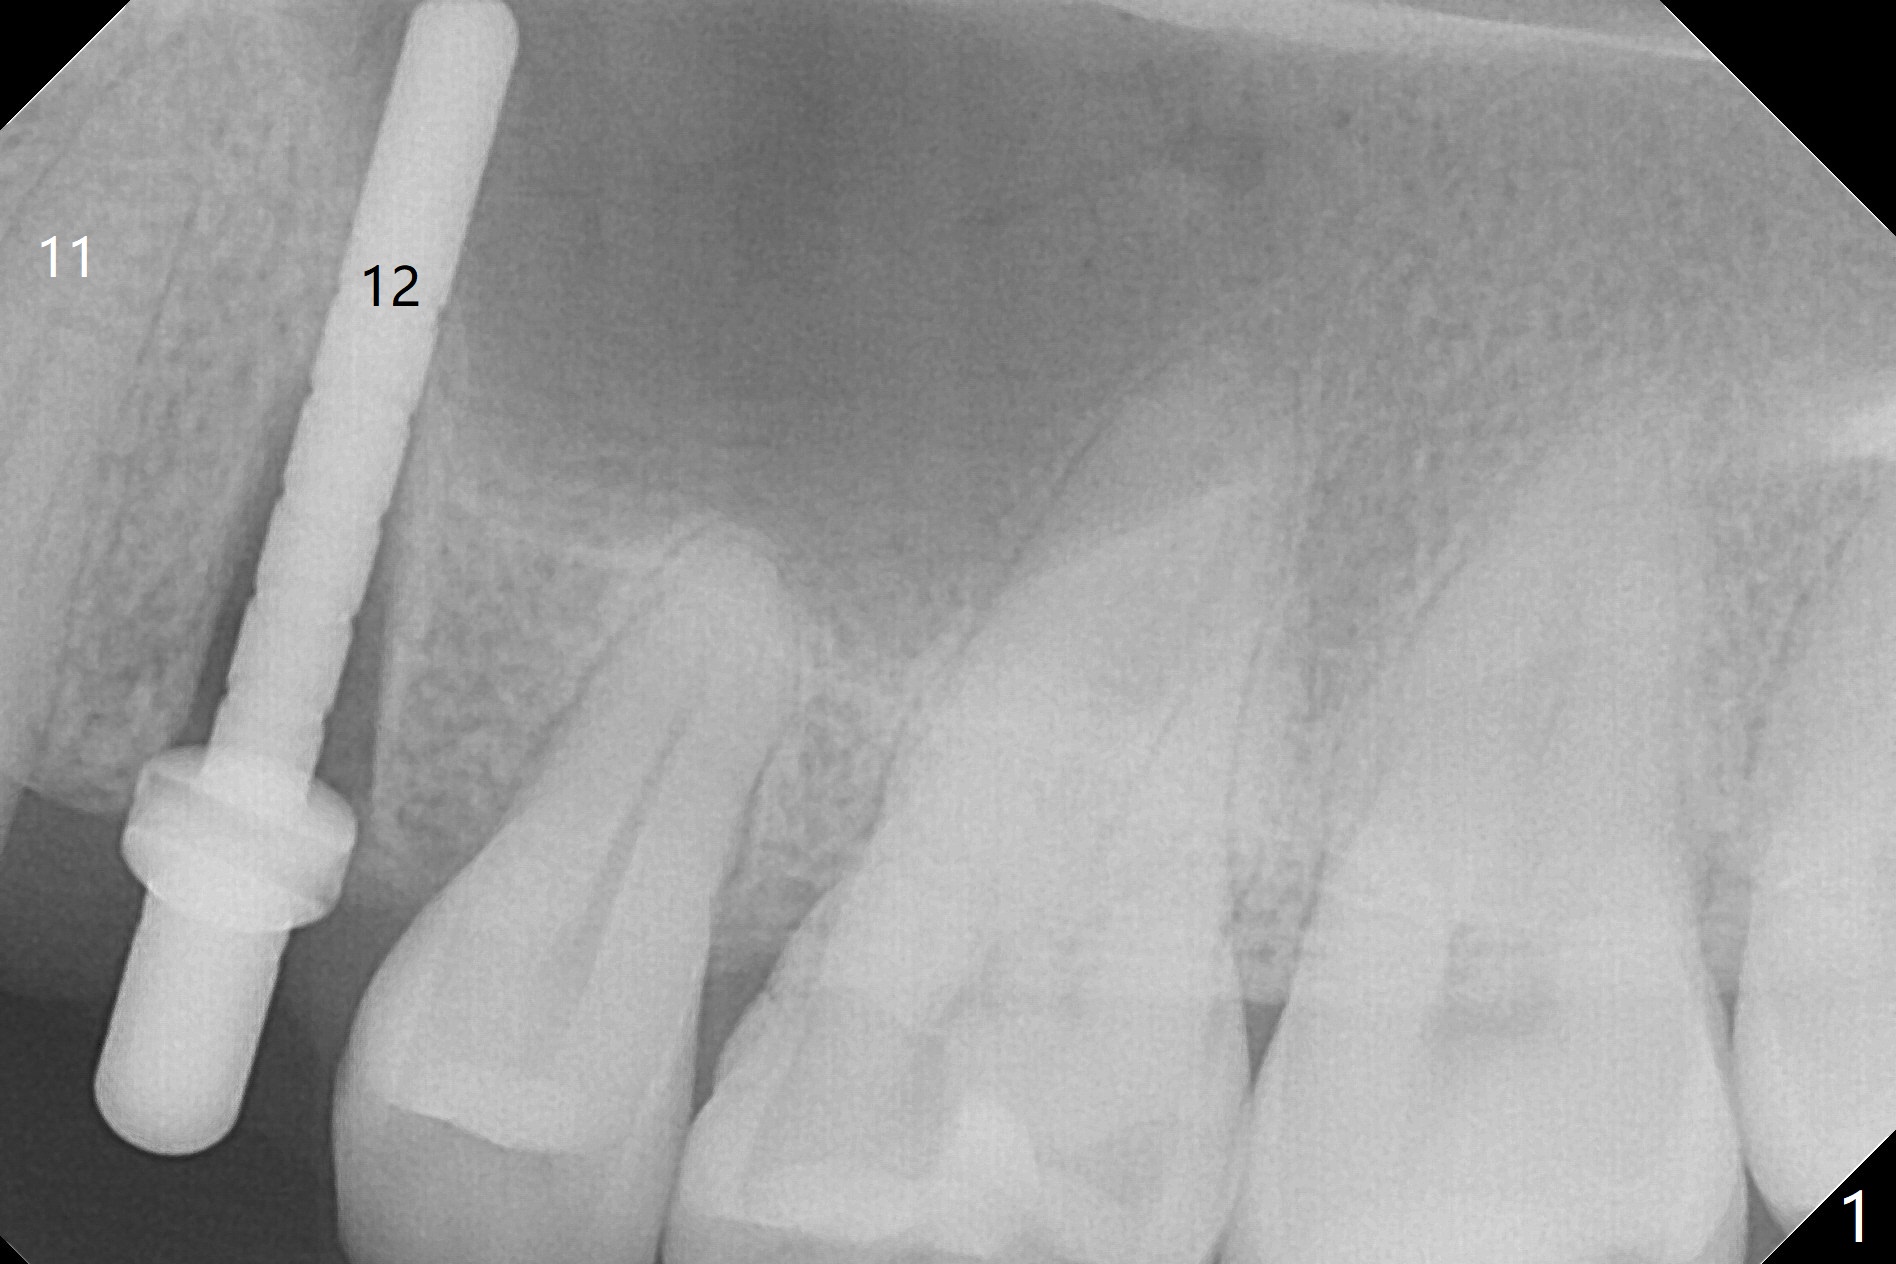

After extraction of the residual roots at #12 and crown prep at #11, osteotomy at #12 is established with Pointed Lindamann bur and 2.2 mm bur for ~ 15 mm. There feels to be sinus floor perforation; a parallel pin is inserted deeper than expected (Fig.1), but there is no membrane perforation. Following sequential osteotomy, a 4x10 mm dummy implant is placed partially with stability (Fig.2). When the same sized definitive implant is placed subcrestally (Fig.3-5 (*: Vera Graft)), the stability remains (~60 Ncm) in spite of the fact that the trajectory is changed once. The coronal socket does not seem to heal 8.5 months postop, in part due to poor hygiene of splinted provisional (Fig.6).